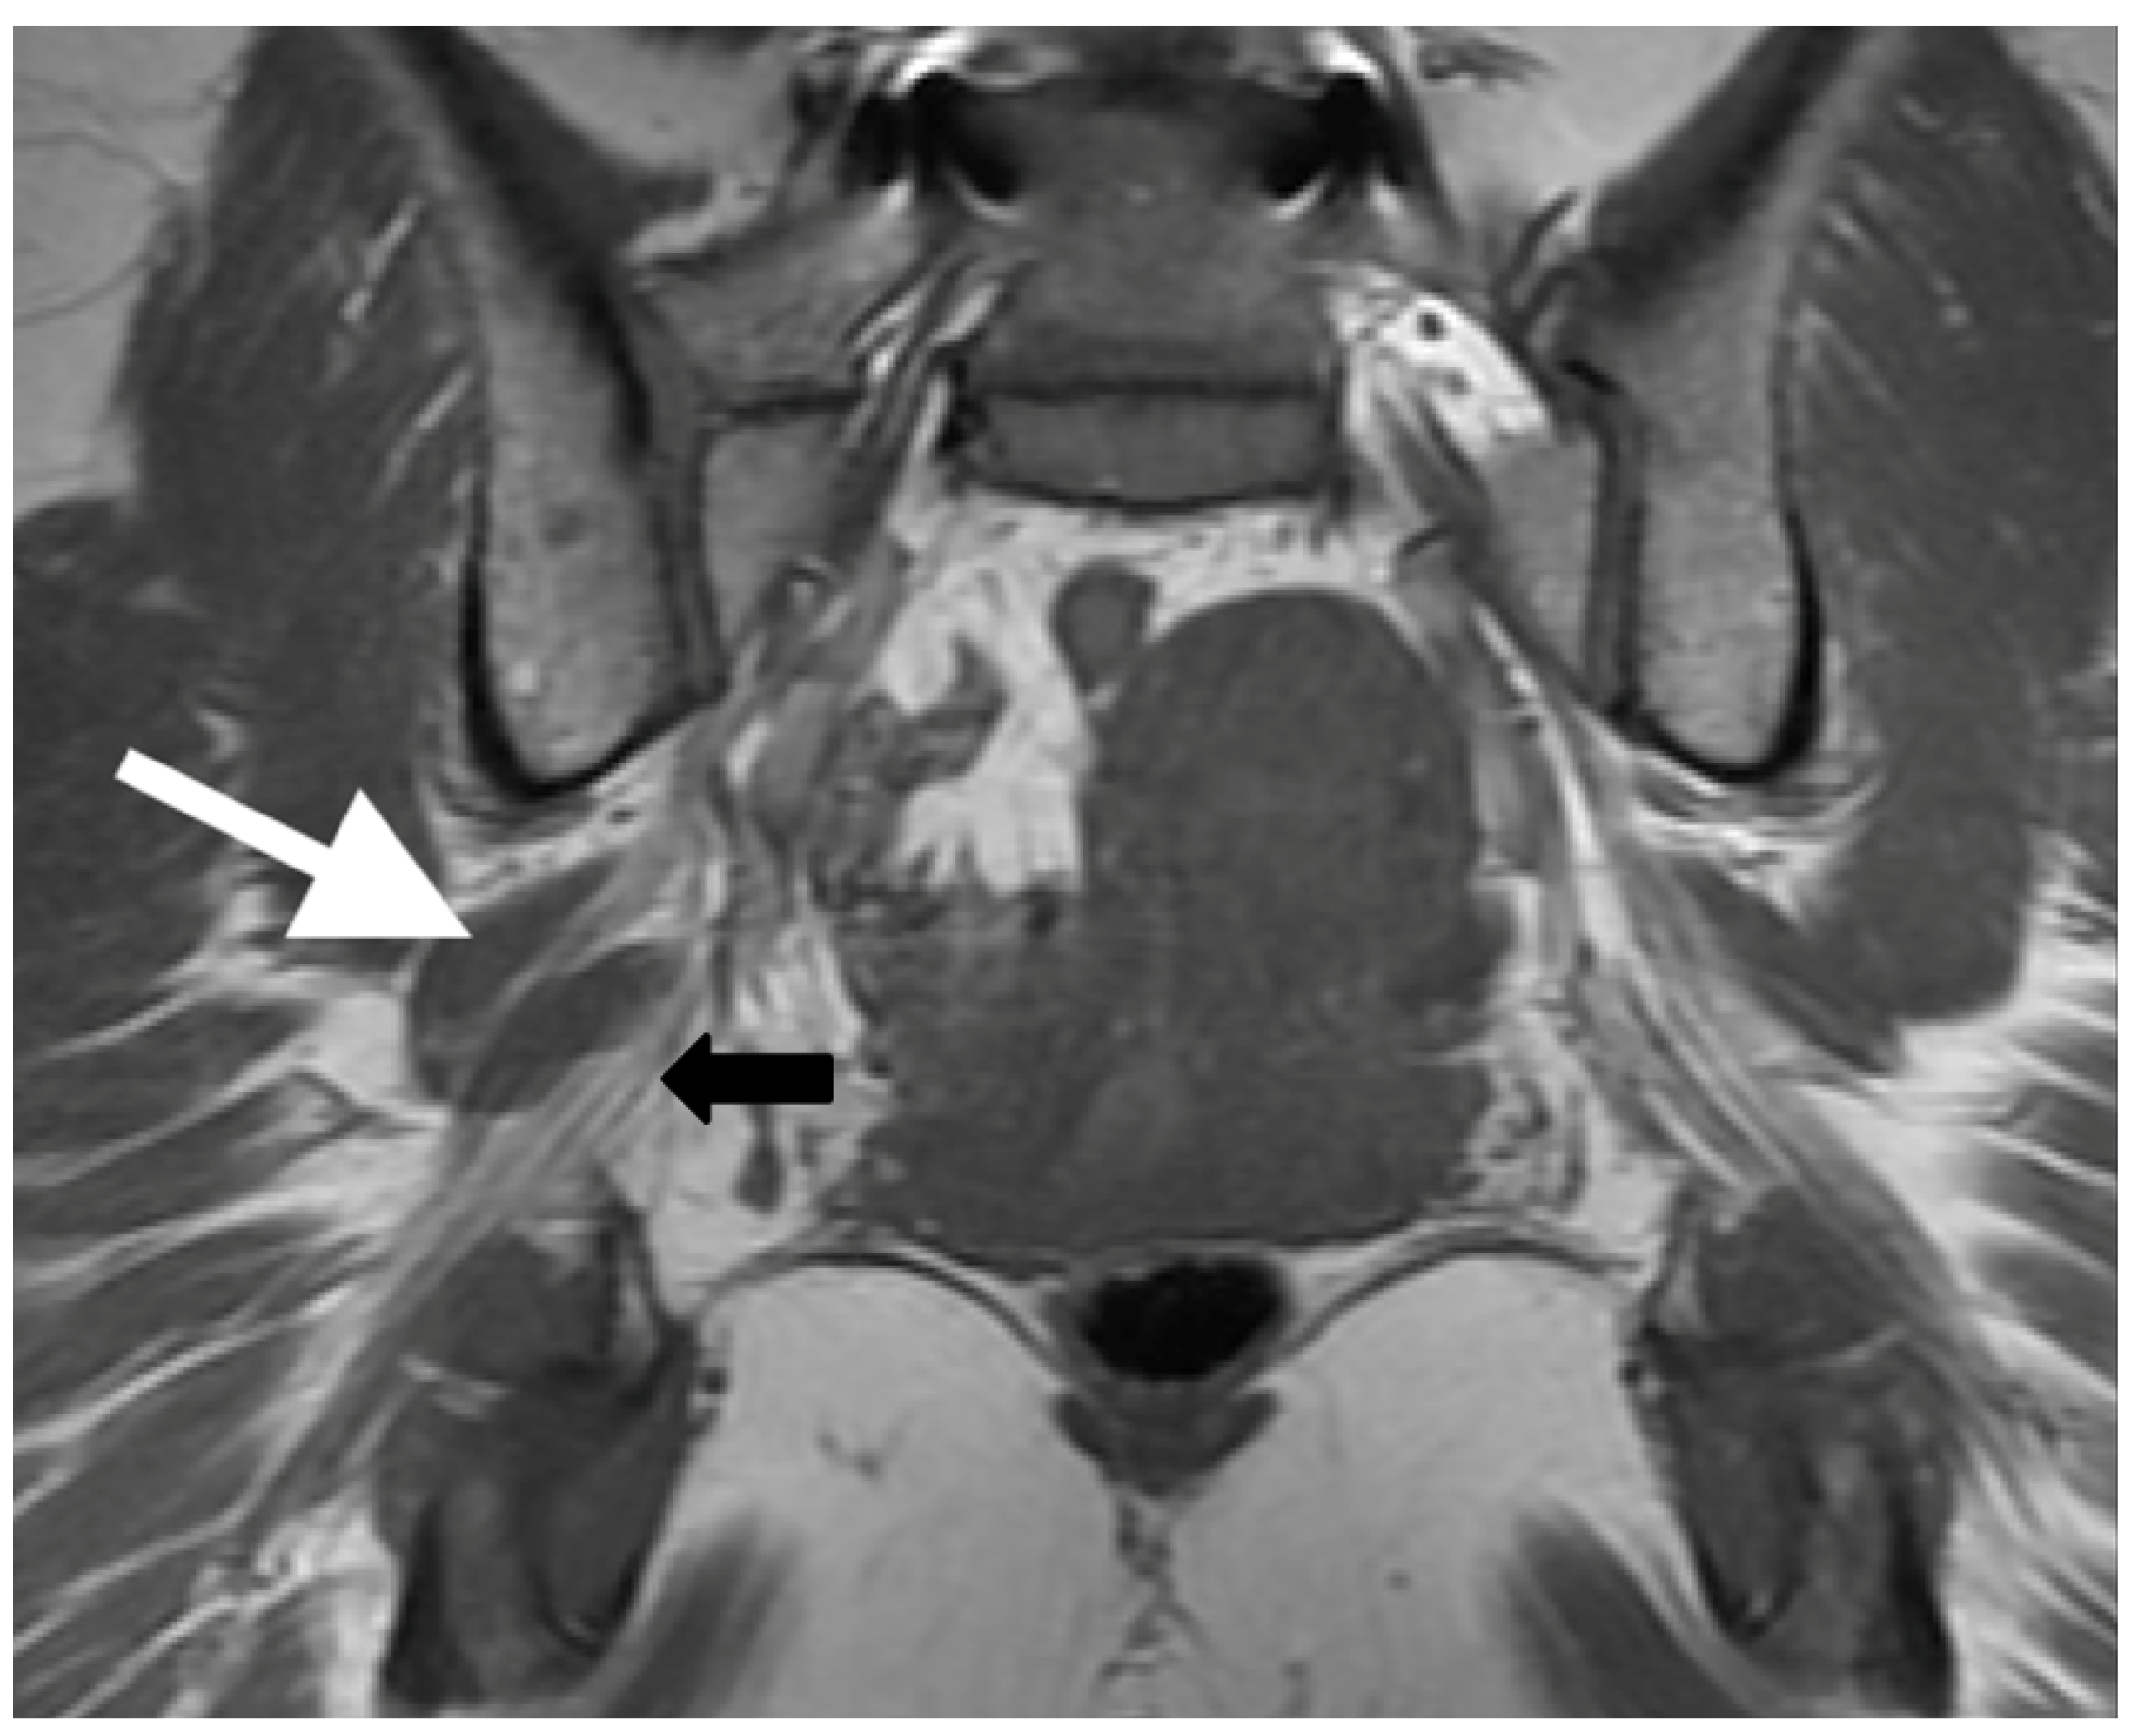

Figure 2.

Magnetic resonance neurogram (MRN) of non-split sciatic nerve (type I). (a) Axial T1-weighted MRN of the sciatic nerve at the level of the sciatic notch demonstrates normal sciatic nerve (black arrow) anterior to the piriformis (white arrow). (b) Coronal T1-weighted sequence showing type I sciatic nerve (black arrow) inferior to the piriformis (white arrow).